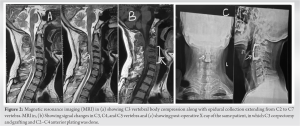

This was followed by grafting and fusion. Graft of appropriate size was harvested from iliac crest in all three cases. Intraoperatively, biopsy samples were taken and pus samples were sent for Ziehl Neelsen staining, Gram staining, culture, and cartridge-based nucleic acid amplification testing (CBNAAT). Postoperatively, ATT was started, and the patient was given hard Philadelphia collar for providing stability to fixation. At the time of discharge, the patient was allowed sitting and walking with Philadelphia collar. Chemotherapeutic response, disease arrest, and healing processes were assessed by clinical findings, laboratory data (ESR), and serial spine radiographs. All three cases were aptly followed up with radiographs, LFT and ESR in view of continuing ATT. First case was a 30-year-old male. He was HCV positive. The patient had injury of upper back 15 months ago from the time of presentation due to which he had wound for which he took treatment from a quack. After 6 months, the patient developed discharging sinus on upper back, for which incision and drainage were done by the same person. After 4–5 months, the patient started complaining of neck and shoulder pain and weakness of bilateral upper limbs. Power was 2/5 at bilateral shoulder, elbow and wrist with decreased palmar grasp. MRI showed peripherally enhancing collection in anterior epidural space extending from C2 to C7 which was compressing the cord (Fig. 2a). MRI also showed changes involving C2, C3, and C4 vertebra with reduced height of C3 vertebra (Fig. 2b).

Atlantoaxial interval was maintained. Based on the MRI, provisional diagnosis of Pott’s disease was made. Because of the patient’s precarious neurologic state, it was decided to decompress the cervical cord immediately. Anterior Smith Robinson approach was taken. C3 corpectomy and decompression by the above mentioned method followed by anterior grafting and plating from C2 to C4 (Anterior Cervical Discectomy and Fusion) was done (Fig. 2c). CBNAAT and biopsy came out to be positive and ATT was started to be continued for 18 months. On follow-up at 6 weeks, ESR was 74, hand grip had improved and power at wrist, elbow, and shoulder was 3/5. At 3 months, ESR was 54, power at wrist, elbow and shoulder was 4/5. At 6 months, ESR was 18 and power at wrist, elbow and shoulder was 4+. Cervical spine X-ray film showed evidence of graft fusion with no loss of height (Fig. 2c). At the end of 1 year follow-up, the patient had fully recovered motor function with power at wrist, elbow, and shoulder being 5/5 and remained so in bilateral upper limb. In another case, a 46-year-old male came with neck pain and weakness bilateral upper limbs for 2 weeks which was gradually increasing. He was non-diabetic and non-immunocompromised. However, he had a history of chronic alcoholism. There was a history of multiple falls in the past 4 months. The patient was already on ATT since last 20 days. On examination, power in bilateral shoulder was 2/5, while that in bilateral elbow and wrist was 3/5. Power was 5/5 in bilateral lower limbs. MRI showed involvement of C3 to C7 vertebral bodies with anterior epidural collection extending from C2 to C7 causing spinal canal stenosis and compression of the exiting nerve roots (Fig. 3a).